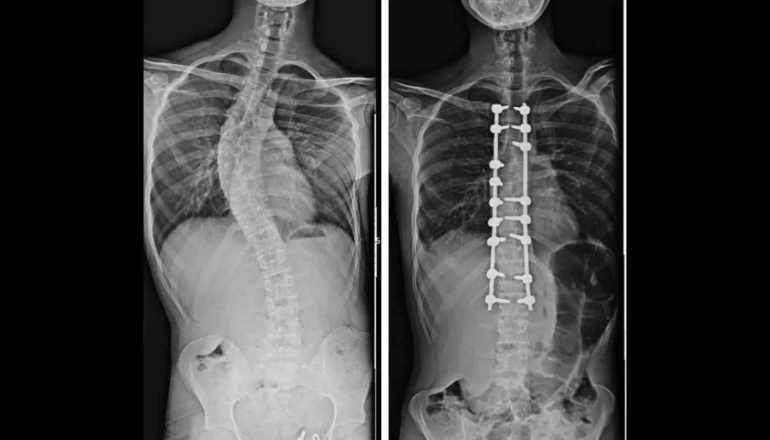

OMÜ Tıp Fakültesi Ortopedi ve Travmatoloji Anabilim Dalı Öğretim Üyesi Doç. Dr. Hüseyin Sina Coşkun, ortopedi alanında kullanılan yapay zeka ve robot teknolojilerine ilişkin bilgi verdi. Özellikle çocuklarda yapılan erken müdahale ile doğru tedavinin önemini vurgulayan Doç. Dr. Coşkun, "Çocukluk çağında görülen ortopedik rahatsızlıklarda erken tanı büyük önem taşıyor. Düz tabanlık, skolyoz, kalça çıkıklığı gibi sorunlar küçük yaşlarda tespit edildiğinde erken müdahale çok önemli oluyor. Ancak günümüzün önemli bir gerçeği var; tablet ve telefon kullanımının artmasıyla birlikte duruş bozuklukları ciddi şekilde çoğaldı. Telefon ve tabletle uzun süre vakit geçiren çocuklarda hareketsizlik artıyor, bu da omurga yapısını ve genel vücut duruşunu olumsuz etkiliyor. Hareketsiz yaşam tarzına bağlı olarak pek çok ortopedik rahatsızlık daha erken yaşlarda görülmeye başlandı” diye konuştu.

Uzun yıllardır yapay zeka ve robot teknolojileri ile tespit ve tedavi yöntemi uyguladıklarını söyleyen Doç. Dr. Coşkun, “Bizde robot teknolojisi bir süredir aktif olarak kullanılıyor ve yapay zeka da ortopedi alanında giderek daha fazla yer buluyor. Özellikle tedavi planlaması aşamasında yapay zeka destekli sistemlerden faydalanılıyor. Yapay zeka, hangi tedavi yönteminin hangi hasta için daha uygun olduğu, hangi yöntemlerin tercih edilmemesi gerektiği ve uygulanacak tedavinin uzun vadede nasıl sonuçlar doğurabileceğinin öngörülmesi konularında önemli katkılar sağlıyor. Bu teknolojiler sayesinde daha kişiselleştirilmiş ve doğru tedavi planları oluşturulabiliyor. Yapay zekanın ortopedideki kullanım alanı oldukça geniş. Özellikle küçük çocukların tedavisinde, omurga ve omurilikle ilgili hastalıklarda bu teknolojilerden yoğun şekilde yararlanılıyor” ifadelerini kullandı.

Küçük çocuklarda duruş bozukluğu, kamburluk ve skolyoz gibi problemlerin geçmiş yıllara göre arttığını belirten Dr. Coşkun, şöyle konuştu:

"Bu tür rahatsızlıklar son derece önemli ve ne kadar erken müdahale edilirse tedavi süreci o kadar başarılı oluyor. Ortopedik hastalıklarda en önemli nokta, mümkünse hastalığın hiç ilerlememesini sağlamak. Önleyici yaklaşımlar bu nedenle büyük değer taşıyor. Ancak bir hastalık ortaya çıkmışsa da erken tanı sayesinde çok daha hızlı ve etkili bir şekilde tedavi sürecine başlanabiliyor."